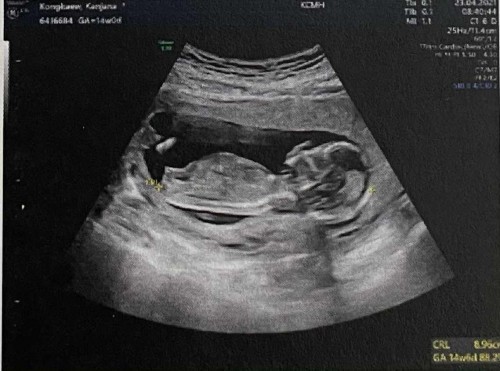

เราเอ็กซเรย์ปอดไปครั้งนึง(ที่เป็นรถเคลื่อนที่) แล้วไม่ได้แจ้งจนท.บนรถว่าตั้งครรภ์อยู่ จะเป็นอันตรายกับน้องไหมคะ คือเราติดcovid-19 ค่ะ แล้ววันนั้นเป็นวันแรกที่หิ้วกระเป๋าออกจากบ้านถูกส่งมารักษาตัว ก่อนเข้าที่พักเขาให้เอ็กซเรย์ปอดก่อน จังหวะนั้นลืมแจ้งจริงๆ ค่ะ (แต่ก่อนหน้านี้คือ บอกจนท. ตลอดว่าท้องอยู่ กำชับเรื่องยาที่ต้องกินมากๆๆ) ตอนนี้เราเอ็กซเรย์รอบที่ 2 แล้ว (รอบนี้แจ้งจนท.บนรถ เขาให้ใส่เหมือนผ้าคลุมที่มีแผ่นตะกั่วอยู่ข้างใน) แต่เราก็ยังกังวลกับการเอ็กซเรย์รอบแรกอยู่เลยค่ะ แล้วตอนนี้ถึงจะมีแผ่นตะกั่วกั้นไว้ แต่ในการเอ็กซ์เรย์ครั้งต่อๆ ไป อีก จะมีอันตรายไหมคะ (ตอนนี้ 16 week ค่ะ / ได้เข้ารับการกักตัวใน Hospitel 4วันแล้ว) : ภาพน้องตอน 14 week ค่ะ #ขอบคุณล่วงหน้านะคะ #ใครมีประสบการณ์ #ขอบคุณสำหรับคำตอบค่ะ